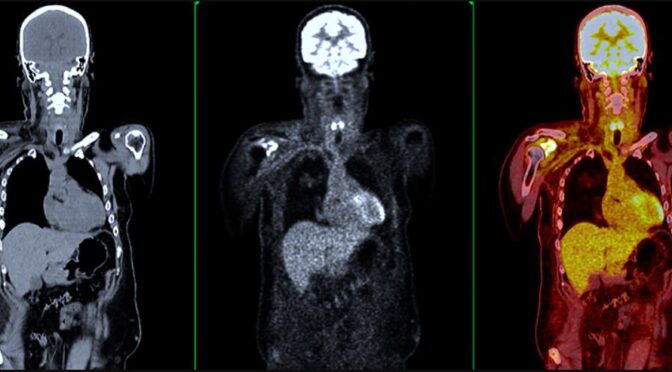

3. CT Scan or MRI: Used to assess tumor size, location, and possible spread to other tissues.

3. Quantitative CT Scan – Provides 3D images and measures bone strength in the spine.

During a bone density test for cancer, patients lie on a padded table while a scanner passes over the body, emitting low-dose X-rays. The procedure typically lasts about 10–20 minutes and is painless. The test results help doctors: